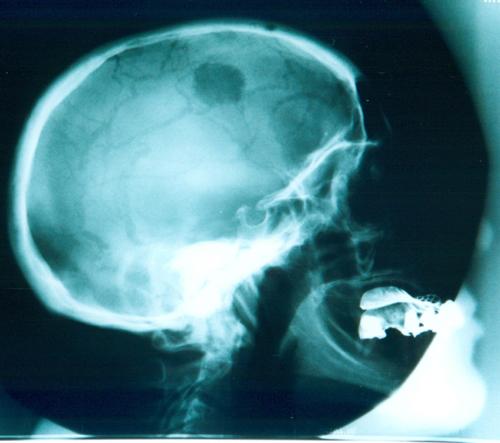

Skull radiograph showing a lytic breast metastasis